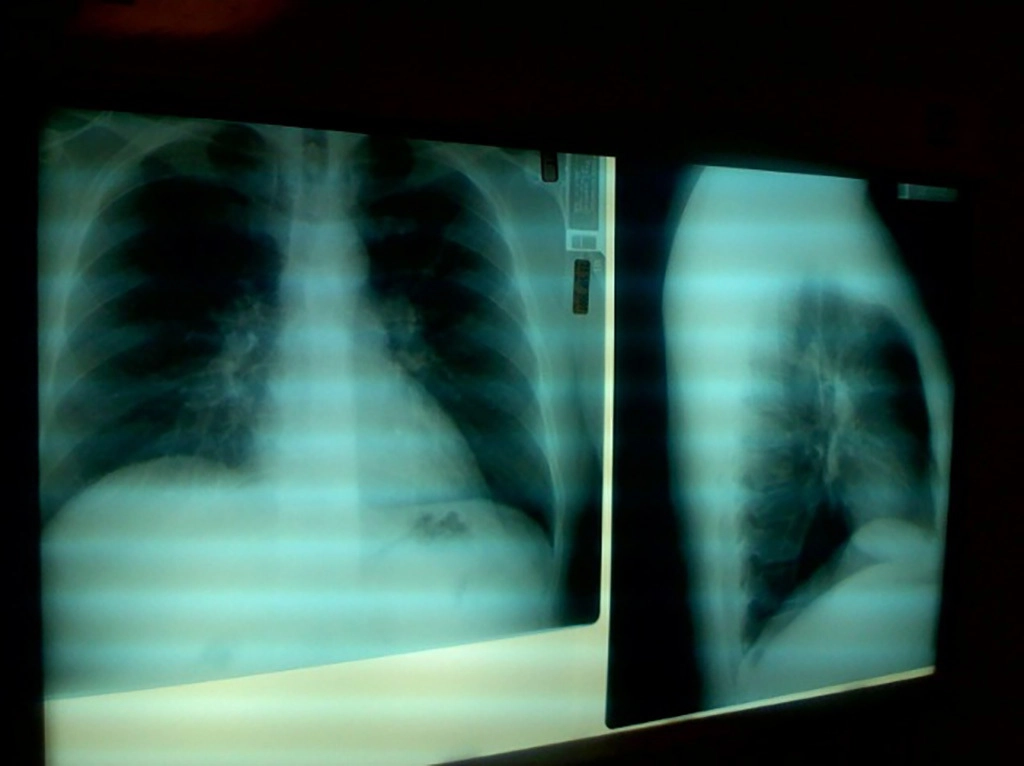

Воспаление легких

Пневмония может вызвать боль и давление в грудной клетке, которые усиливаются, когда человек кашляет или глубоко дышит. Помимо боли в груди, для пневмонии характерны: интенсивный кашель; сбивчивое дыхание; высокая температура тела, которую сложно сбить обычными жаропонижающими средствами.